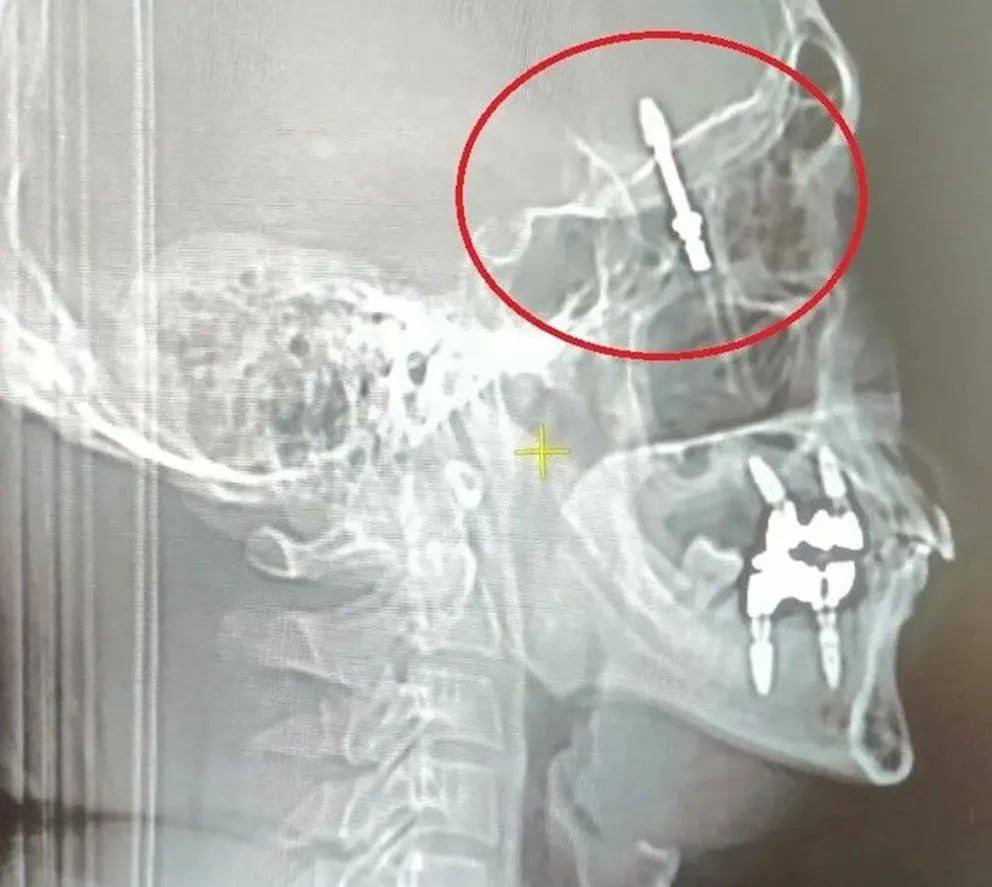

40-річний чоловік в Туреччині звернувся до приватної клініки, щоб йому вирвали хворий зуб і встановили замість нього імплант.

Під час операції обладнання для встановлення імпланта вийшло з ладу, тож лікар вирішив діяти вручну, однак вгвинтив імплант із такою силою, що проломив кістки черепа і потрапив у мозок. Після цього чоловіка відвезли у лікарню.